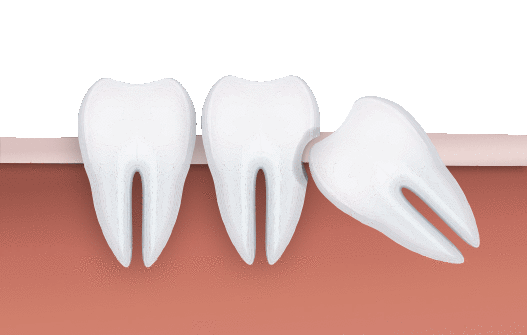

外面拔時易斷裂於骨頭內而難以取出